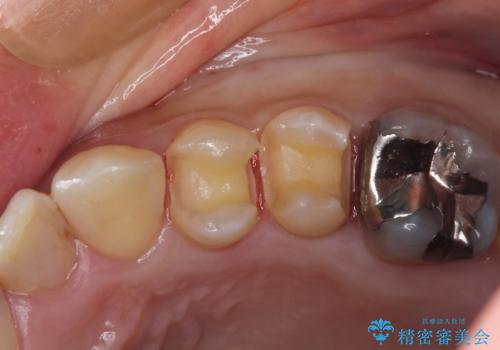

- 笑って見えるところの金属を白くしたいとのことで来院されました。

相談の結果、左上4,5のメタルインレーをセラミックインレーへと変更することとしました。

左上6は希望されなかったため、左上4,5のみをセラミックにやりかえています。